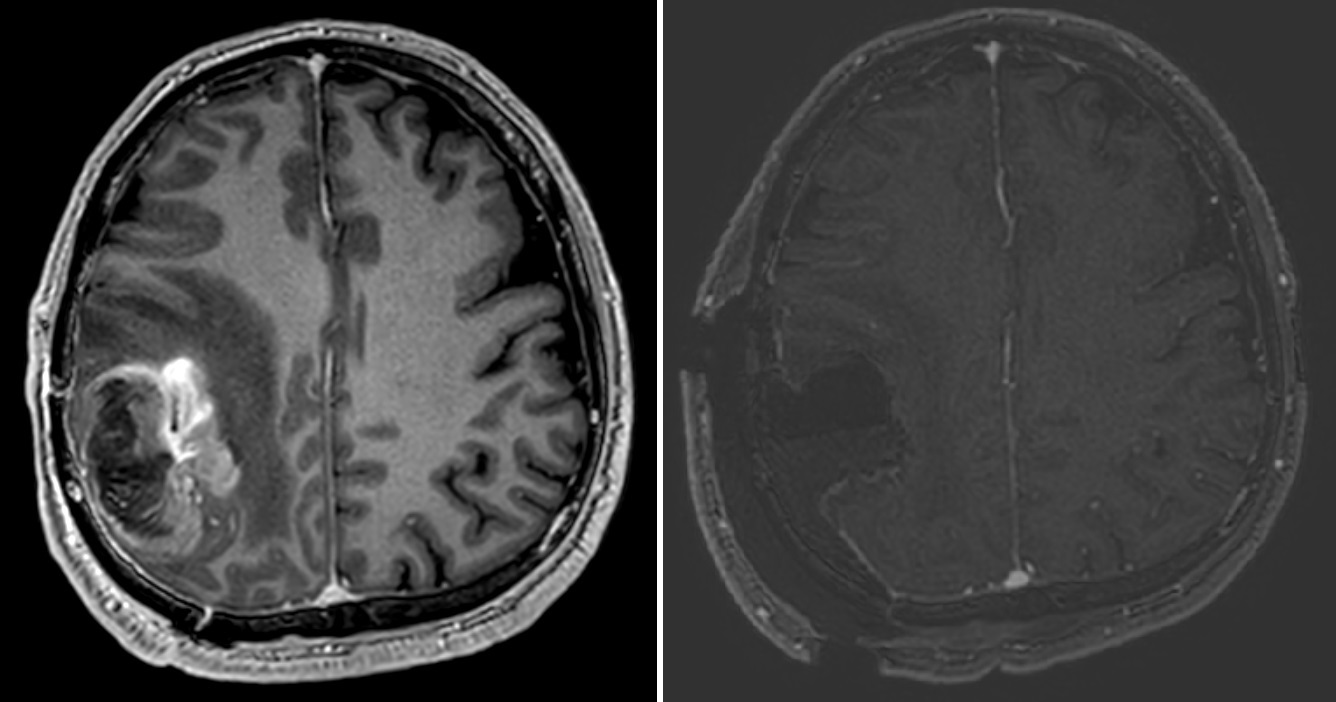

U dospelých pacientov je najčastejším gliómom malígny glioblastóm. Liečba glioblastómu spočíva v chirurgickej resekcii nádoru, po ktorom nasleduje konkomitantná chemorádioterapia. Aj keď v súčasnosti nie je možné nádor vyliečiť, radikálne odstránenie nádoru (zobrazený na MR vyšetrení ako T1 enhancujúci nádor) vedie k lepšej kontrole ochorenia a je spojené s predĺžením prežívania.